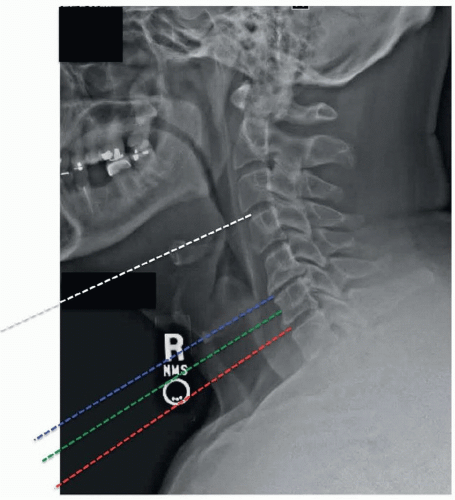

For procedures involving C4 and above, nasotracheal intubation can be considered in select patients to facilitate access by allowing dental apposition. The need for this can be assessed by examining the position of the mandible with respect to the line of sight to the desired disk space on a preoperative lateral x-ray.

Approximate location of incision can also be estimated on the basis of distance between mandible and sternum on preoperative lateral x-ray (Figure 1-7).